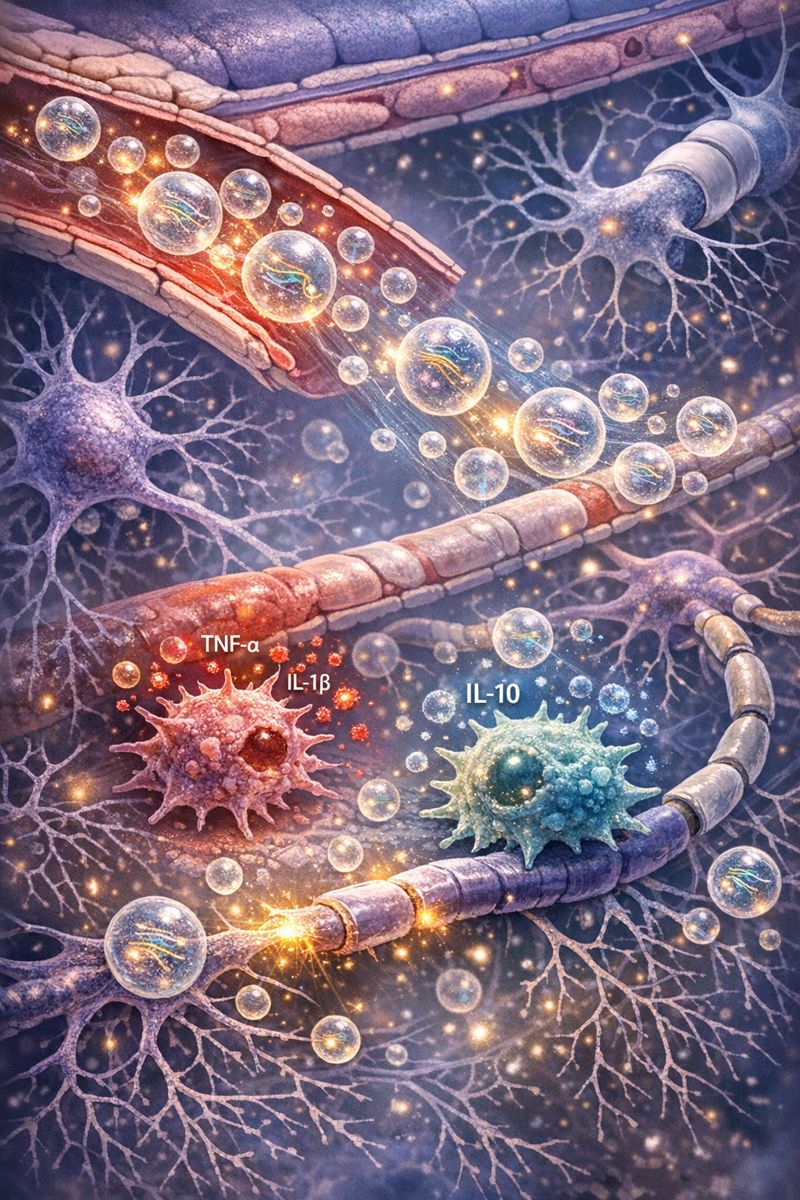

Đội ngũ có kinh nghiệm trong tế bào gốc, miễn dịch học, công nghệ sinh học, y học phân tử